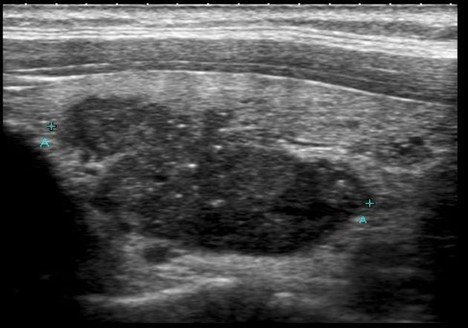

Papillary Thyroid Cancer Ultrasound from nbubg. Ultrasound can reveal a mass in the thyroid but can not give definite diagnosis of cancer. An ultrasound scans use high frequency sound waves to create a picture of a part of the body.

Thyroid ultrasound scans are safe and effective ways to produce images of the thyroid gland. Transverse grey scale sonogram shows a solid ill-defined hypoechoic nodule arrows containing punctate calcification arrowheads in the right lobe of thyroid gland. Thyroid nodules were found in 97 of patients with thyroid cancer and in 56 of without.

A thyroid ultrasound is a safe painless procedure that uses sound waves to examine the thyroid gland. An ultrasound also known as ultrasonography sonography or sonogram helps doctors look for tumors in certain areas of the body that dont show up well on x-rays. Solid nodule and size larger than 2 cm can be.